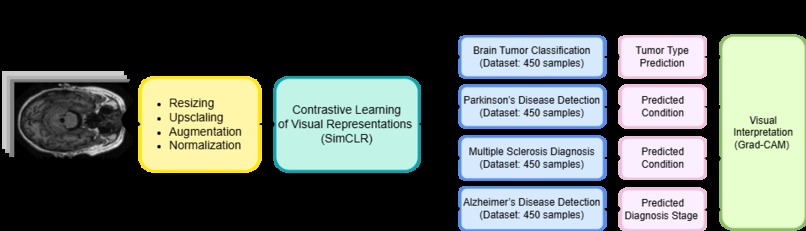

Project Architecture

- Collected and preprocessed large-scale unlabeled brain MRI slices

- Designed medically safe data augmentations to preserve anatomical features

- Implemented SimCLR with a from-scratch developed ResNet-50 backbone for self-supervised pretraining

- Fine-tuned the pretrained encoder using very small labeled datasets (as few as 450 images per class)

- Integrated Grad-CAM for visual explanations and added quantitative explainability metrics

- Evaluated performance across multiple brain disease classification tasks